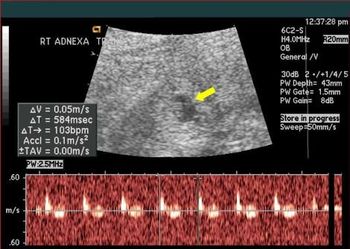

A 29-year-old gravida 10, para 3 (1 term gestation, 1 preterm gestation of twins, 1 stillbirth at 5 months, 2 spontaneous abortions, and 4 elective abortions) presented to the clinic at about 5 weeks’ gestation with abdominal pain and vaginal bleeding. She described the pain as sporadic, mostly on the left side, exacerbated by movement, and resolving with rest, and the bleeding as initially intermittent but then heavier “like a period.”